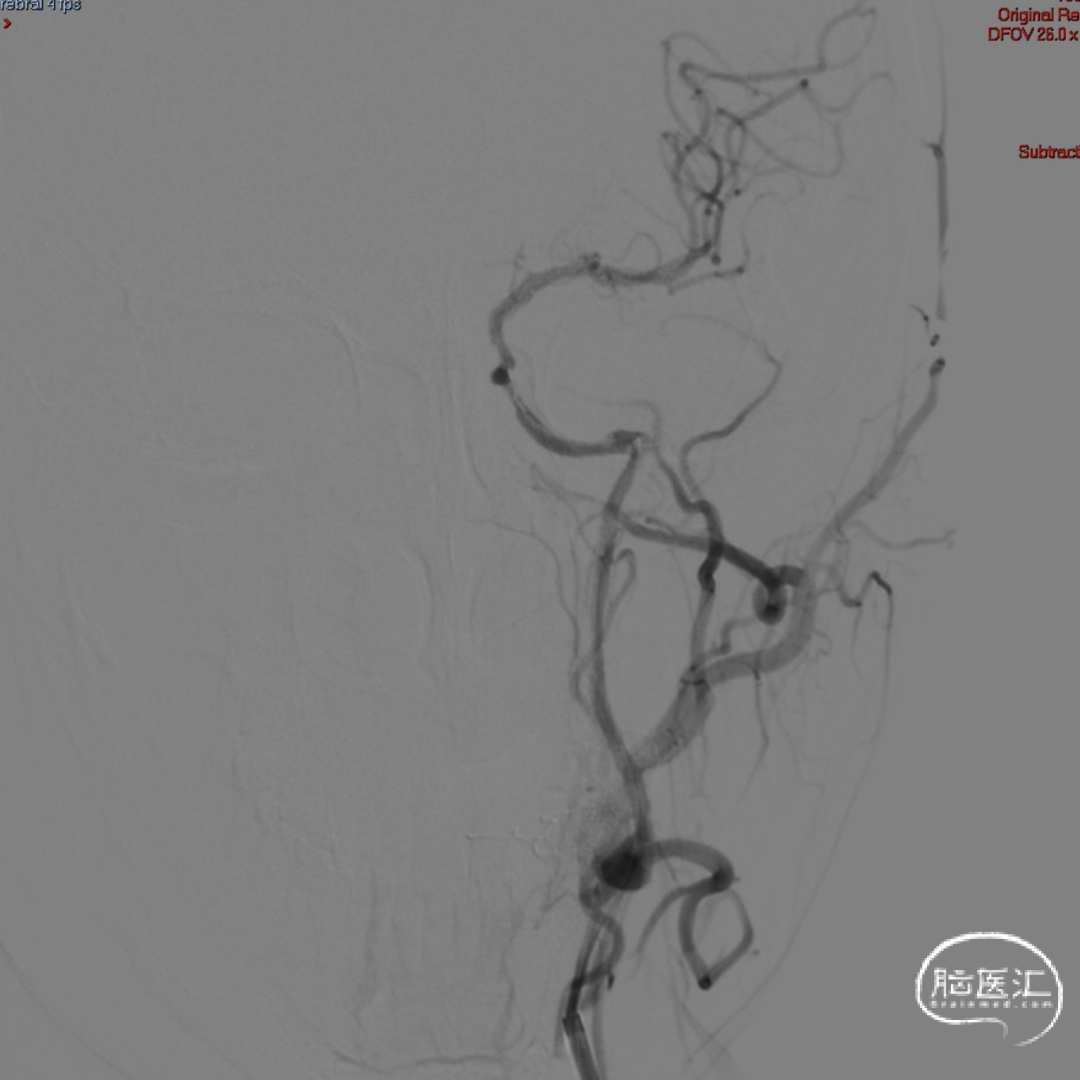

术后即刻影像。

支架植入后造影提示残余狭窄约10%。术中患者生命体征稳定,术后患者恢复良好出院,继续抗血小板聚集及他汀类药物治疗。